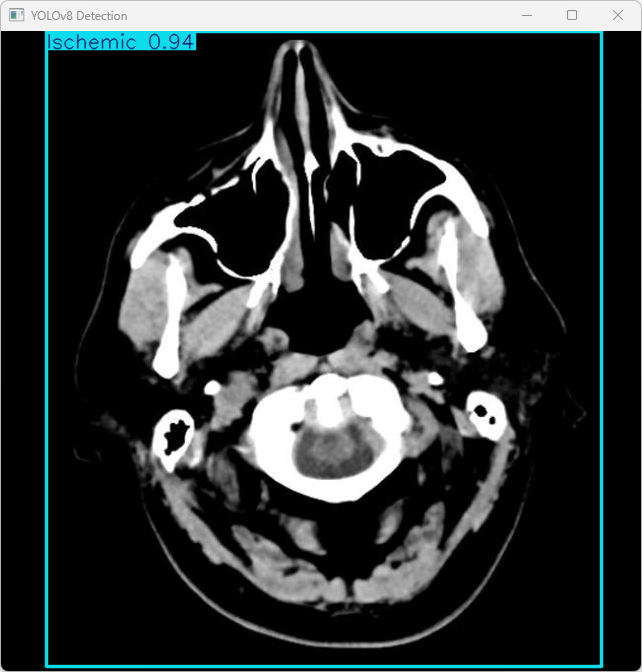

执行imgTest.py代码后,会将执行的结果直接标注在图片上,结果如下:

这段输出是基于YOLOv8模型对图片“imagetest.jpg”进行检测的结果,具体内容如下:

图像信息:

(1)处理的图像路径为:TestFiles/imagetest.jpg。

(2)图像尺寸为640×640像素。

检测结果:检测到 1 个 Ischemic(缺血性脑中风)

处理速度:

(1)预处理时间: 11.5 毫秒

(2)推理时间: 11.5 毫秒

(3)后处理时间: 122.7 毫秒

总结:

系统成功检测到图像中的缺血性中风(Ischemic)类型。